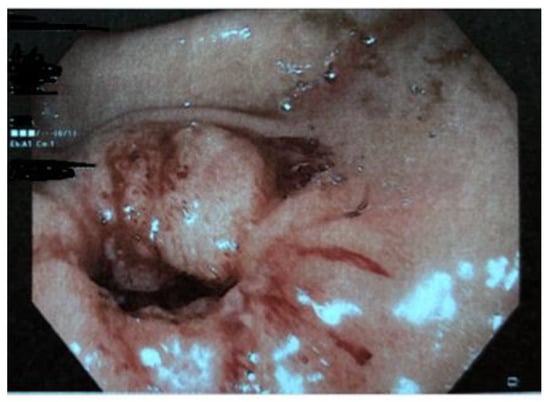

| Boybeyi et al. [16], 2010 | 11 | 3,6 (2–8) years (mean age, range) | Vomiting (5 cases) Vomiting + abdominal pain (4 cases) Vomiting + weight loss (2 cases) | US + UGI series (6 cases), UGI series (5 cases), EGDS | Gastric edema and hyperemia (2 cases) | EBD (4 cases)–EBD + B-I (1 case)–B-I (6 cases) |

| Bartlett et al. [19], 2018 | 1 | 12 years | Vomiting, failure to thrive | EGDS, US. | Previous history of eosinophilic esophagitis. Gastritis. | EBD + Botulinum injection (failure) HMP + temporary gastrostomy |